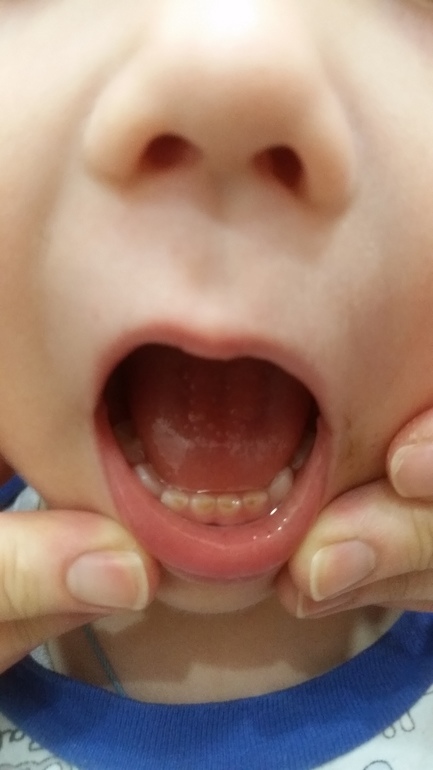

Иллюстрации флюороза молочных зубов